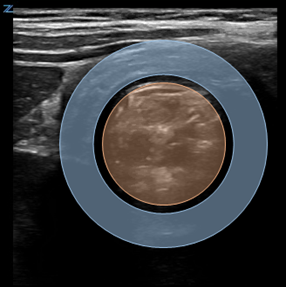

Classically, intussusception manifests in the transverse orientation as a ‘target sign’ or ‘donut sign’ (Figure 1) representing layers of intestine within the intestine. In the longitudinal orientation, the layers of intestine appear as a ‘pitchfork’ or ‘submarine sandwich’ (Figure 2). These findings are most commonly seen in the right lower quadrant for ileocolic intussusception, which is the most common type of intussusception. Small bowel intussusceptions can be differentiated by their size, which are often ≤3 cm.5 While small bowel intussusceptions often spontaneously reduce, if symptoms and findings persist, computed tomography (CT) may be necessary to determine management. POCUS is useful in differentiating variants of intussusception that range from a surgical emergency to a transient source of abdominal pain allowing clinicians to better manage these patients.6

Figure 1. Target Sign on cross-sectional image of intussusception